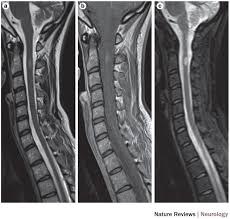

Abnormalities show up on scans from many illnesses other than ms. A multiple sclerosis diagnosis may not always be made solely on the basis of mri. An mri scan is the best way to locate multiple sclerosis (ms) lesions (also called plaques) in the brain or spinal cord. Magnetic resonance imaging (mri) has played a central role in the clinical management and scientific investigation of multiple sclerosis (ms) and has become the most important ancillary tool for diagnosing and monitoring the disease. The clinical usage of … In fact, researchers and medical professionals consider mri to be one of the biggest breakthroughs in the field of multiple sclerosis, since it makes it possible to see lesions on the brain and spinal cord. Sponsored by the consortium of ms centers, an international group of neurologists, radiologists, and imaging. Multiple sclerosis (ms) is a relatively common acquired chronic relapsing demyelinating disease involving the central nervous system, and is the second most common cause of neurological impairment in young adults, after trauma 19. Since its technical development in the early 1980s, magnetic resonance imaging (mri) has quickly been adopted as an essential tool in supporting the diagnosis, longitudinal monitoring, evaluation of therapeutic response, and scientific investigations in multiple sclerosis (ms). Mri is an important diagnostic tool for multiple sclerosis because it produces images of lesions in the brain and spinal cord. These lesions can appear as the condition progresses, and they may. The diagnosis is made from a combination of clinical, imaging, and laboratory findings patients with ms can present with motor, sensory, visual, and/or autonomic pathway symptoms Magnetic resonance imaging (mri) is one of the most important and most commonly used tools for diagnosing and monitoring multiple sclerosis (ms).

Since its technical development in the early 1980s, magnetic resonance imaging (mri) has quickly been adopted as an essential tool in supporting the diagnosis, longitudinal monitoring, evaluation of therapeutic response, and scientific investigations in multiple sclerosis (ms). Morphology and evolution of cortical lesions in multiple sclerosis. Magnetic resonance imaging (mri) is one of the most important and most commonly used tools for diagnosing and monitoring multiple sclerosis (ms). Magnetic resonance imaging (mri) plays a crucial role in multiple sclerosis (ms) diagnosis, disease monitoring, prognostication, and research. The clinical usage of … Brain mri scan showing multiple sclerosis lesions. An mri scan is the best way to locate multiple sclerosis (ms) lesions (also called plaques) in the brain or spinal cord. Magnetic resonance imaging (mri) has developed into the most important tool for the diagnosis and monitoring of multiple sclerosis (ms).

Widespread use of mri (magnetic resonance imaging) has revolutionized the ability to diagnose multiple sclerosis. Its high sensitivity for the evaluation of inflammatory and neurodegenerative processes in the brain and spinal cord has made it the most commonly used technique for the evaluation of patients with ms. The clinical usage of … The diagnosis is made from a combination of clinical, imaging, and laboratory findings patients with ms can present with motor, sensory, visual, and/or autonomic pathway symptoms Magnetic resonance imaging (mri) is the gold standard imaging technique for the identification of demyelinating lesions which can be used to support a clinical diagnosis of ms, and ms can now be diagnosed in some patients after a clinically isolated syndrome (cis) using new mri diagnostic criteria. In fact, researchers and medical professionals consider mri to be one of the biggest breakthroughs in the field of multiple sclerosis, since it makes it possible to see lesions on the brain and spinal cord. Sponsored by the consortium of ms centers, an international group of neurologists, radiologists, and imaging. Morphology and evolution of cortical lesions in multiple sclerosis. It is the preferred imaging method to help establish a diagnosis of ms and to monitor the course of the disease. Magnetic resonance imaging (mri) has developed into the most important tool for the diagnosis and monitoring of multiple sclerosis (ms). Mri and ms multiple sclerosis (ms) is a condition in which the body's immune system attacks the protective covering (myelin) surrounding the nerves of the central nervous system (cns). Multiple sclerosis multiple sclerosis (ms) is a potentially disabling disease of the brain and spinal cord (central nervous system). An mri scan is the best way to locate multiple sclerosis (ms) lesions (also called plaques) in the brain or spinal cord.